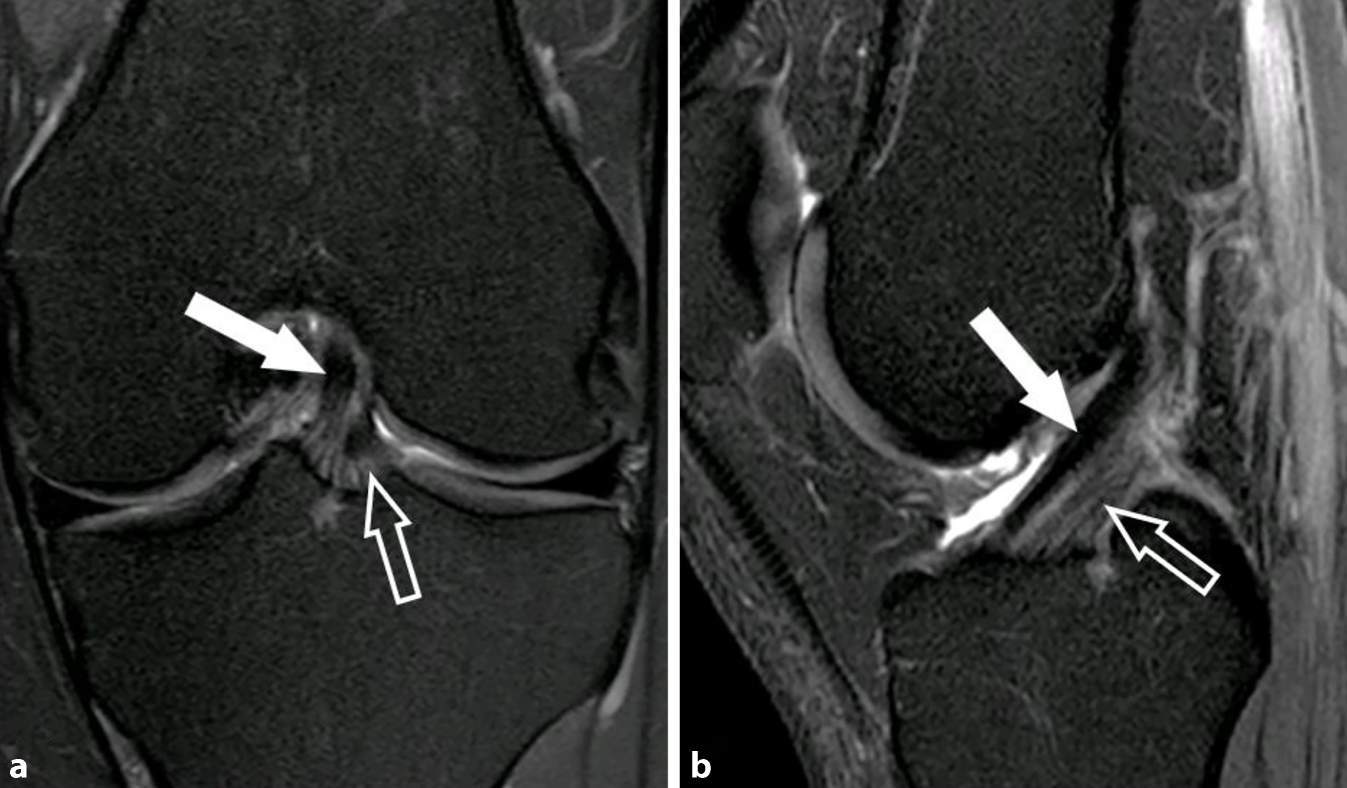

Abb. 6

MRT des Kniegelenks von drei unterschiedlichen Patient:innen nach jeweils akuter Kniedistorsion. Koronale Short-Tau-Inversion-Recovery(STIR)-Sequenzen mit Schnittführung und Vergrößerung des anterolateralen Kompartiments mit Darstellung des anterolateralen Ligaments. a Intaktes anterolaterales Ligament (ALL) mit flacher, hypointenser Konfiguration (weißer Pfeil) und normaler distaler Insertion (hohler Pfeil), welches sich durch die umgebenden Weichteilödeme gut demaskiert. b Partialruptur des ALL mit partieller Faserunterbrechung an der tibialen Insertion (hohler Pfeil) und Verdickung des distalen Ligamentanteils (weißer Pfeil). c Vollständige Ruptur des ALL mit Ablösung von der tibialen Insertion (hohler Pfeil), geringer Retraktion und welliger Konfiguration (weißer Pfeil) sowie umgebenden Ödemen. In Bild b und c ist jeweils eine Ruptur des vorderen Kreuzbands partiell mitabgebildet (Pfeilspitzen), mit welcher eine Verletzung des ALL typischerweise assoziiert ist